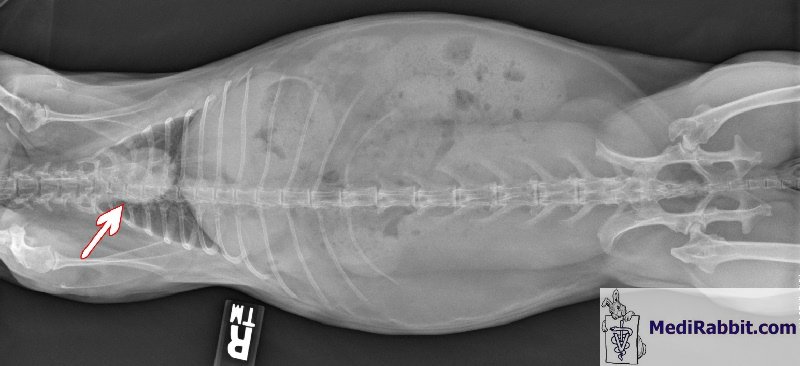

Radiografia okolicy brzusznej

królika

Zdjęcie

rentgenowskie okolicy brzusznej królika jest często wykonywanym badaniem

diagnostycznym w przypadku duszności (dyspnoea), brzydkiego lub

ciągłego kaszlu, urazu klatki piersiowej lub w przypadku

podejrzenia zapalenia płuc. Dostarcza informacji na temat kształtu

i rozmiaru serca, płuc. Może wykryć niewydolność

serca, rozedmę (emphysema),

możliwe istnienie ropni lub nowotworów (np.grasiczak- thymoma,

rak płuc) oraz inne stany chorobowe, a także określić

rysunek naczyń. Ta technika ma niestety swoje ograniczenia. Małe

złośliwe guzy mogą być zbyt małe żeby były

widoczne lub zbyt trudne do uwidocznienia. Zatory płucne (skrzepy krwi w

płucach) także nie są do zobaczenia i wymagają

dodatkowych badań.